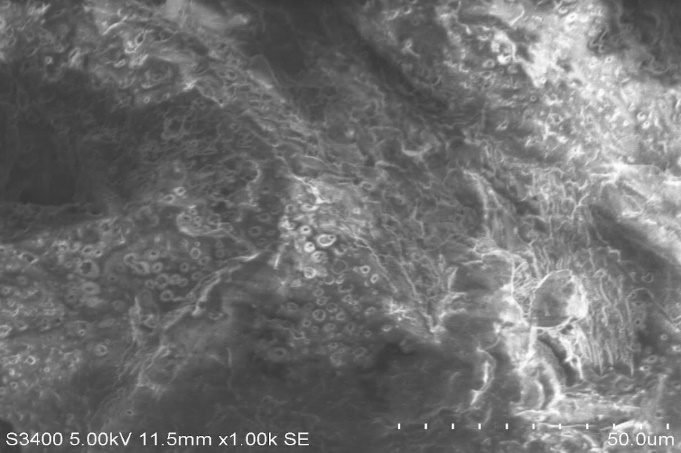

Scanning Electron Microscopy of optimized luliconazole microsponge formulation was carried to determine the surface morphology. The sample was mounted directly onto the SEM sample holder using double sided sticking tape and images were recorded at 11.8 mm X 100SE magnifications at acceleration voltage of 10 kV using scanning electron microscope. Fig. 11 shows the SEM image of microsponge F1 formulation. The porous image of microsponge can be seen in fig. 12 which is recorded at 11.5 X 50.0 SE. So, by this we can say that all microsponge pores are lies in the given range.

Fig. 12: SEM image of porous structure of F1 microsponge